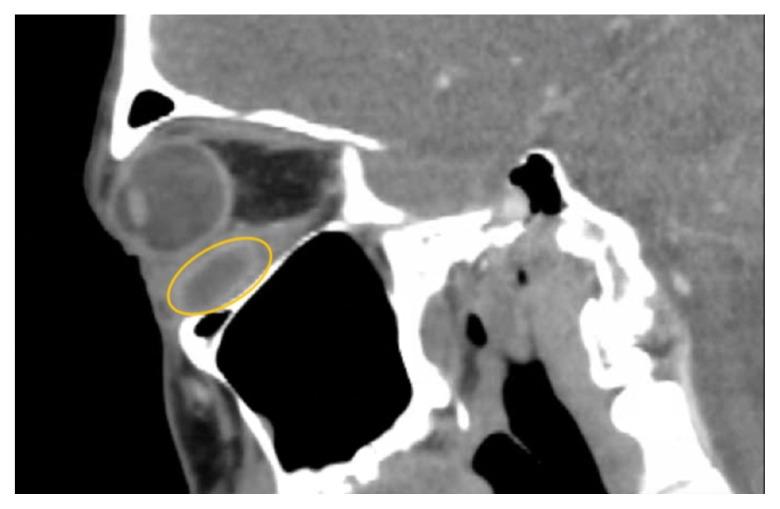

Soft tissue infections, including abscesses, are frequently encountered in the emergency department. However, abscesses of the inferior rectus muscle are rare and may present unique diagnostic and therapeutic challenges due to the scarcity of documented cases. This case report highlights the treatment of a 47-year-old male presenting with an abscess in the left inferior rectus muscle due to an acute Methicillin-resistant Staphylococcus aureus infection. Imaging revealed a distinct fluid collection compressing the left globe, causing restricted ocular motility and other symptoms. Despite prior intravenous antibiotics, the abscess persisted. While intravenous antibiotics are an important component of treatment, this case highlights the potential insufficiency of this approach alone, emphasizing a need for surgical intervention such as orbitotomy for drainage. This report contributes to the limited literature on inferior rectus muscle abscesses and underscores the need for further research and clinical attention to optimize patient outcomes.

软组织感染,包括脓肿,在急诊科很常见。然而,下直肌脓肿很少见,由于记录在案的病例稀缺,可能带来独特的诊断和治疗挑战。本病例报告重点介绍了一名47岁男性因急性耐甲氧西林金黄色葡萄球菌感染导致左眼下直肌脓肿的治疗情况。影像学检查显示有一个明显的液体积聚压迫左眼,导致眼球运动受限和其他症状。尽管之前使用了静脉抗生素治疗,但脓肿仍持续存在。虽然静脉抗生素是治疗的重要组成部分,但本病例突出了仅采用这种方法可能存在的不足,强调了手术干预(如眼眶切开引流)的必要性。本报告丰富了关于下直肌脓肿的有限文献,并强调需要进一步研究和临床关注以优化患者预后。